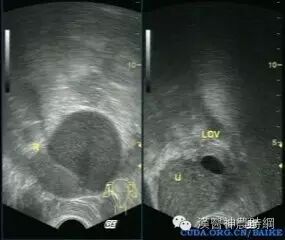

B超声象图:B超显象是目前辅助诊断子宫内膜异位症的有效方法,主要用以观察卵巢子宫内膜异位囊肿,其声象图的特征为:囊性肿块,边界清晰或不清。如囊肿周围粘连重,则边界不清;如囊肿与子宫或周围组织粘连少,则边界清晰。囊肿多为中等大小,囊肿内可见颗粒状细小回声,是囊液粘稠表现。有时因陈旧性血块浓缩机化而出现较密集的粗光点图象,呈混合性肿块状。

肿块常位于子宫后侧,可见囊肿子宫伴随症。囊肿自发破裂时,声象图示后凹陷,囊肿较前缩小。腹腔镜检查:腹腔镜检查是目前诊断子宫内膜异位症的新标准,通过腹腔镜可直接窥视盆腔,见到异位病灶即可明确诊断,且可进行临床分期,以决定治疗方案。